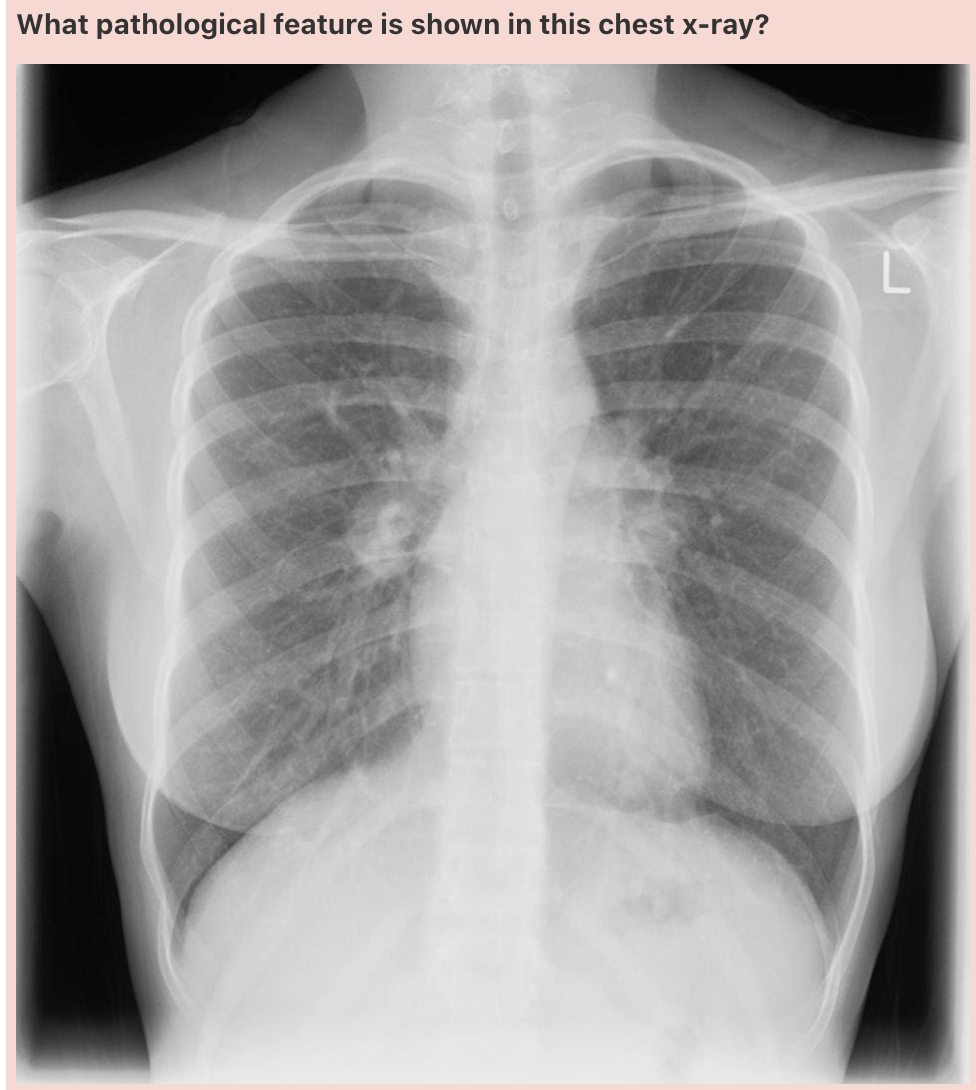

**Answer: Normal**